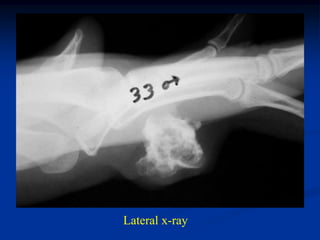

33 year male with soft tissue chondroma finger

Lateral x-ray

Oblique view